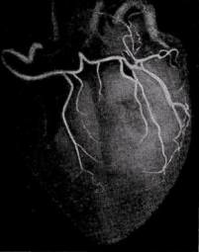

КОРОНАРОГРАФИЯ

Коронарография является признанным "золотым стандартом" для выявления или исключения коронарной болезни сердца. Она позволяет определить выраженность сужения коронарных артерий, его локализацию и количество значительно стенозированных коронарных артерий (критерием такого сужения считается уменьшение площади просвета более чем на 70%)

Разработка и развитие метода селективной коронарографии явились наибольшим стимулом для применения хирургических методов лечения ИБС. Поскольку вопрос о проведении коронарного шунтирования не может быть решен без данных ангиографического исследования, то без селективной коронарографии было бы невозможно развитие коронарной хирургии.

Широкое применение селективной коронарографии и оперативных вмешательств на коронарных артериях сердца в последние годы позволило изучить анатомические особенности коронарного кровообращения живого человека, разработать функциональную анатомию артерий сердца применительно к реваскуляризирующим операциям у больных с ишемической болезнью сердца.